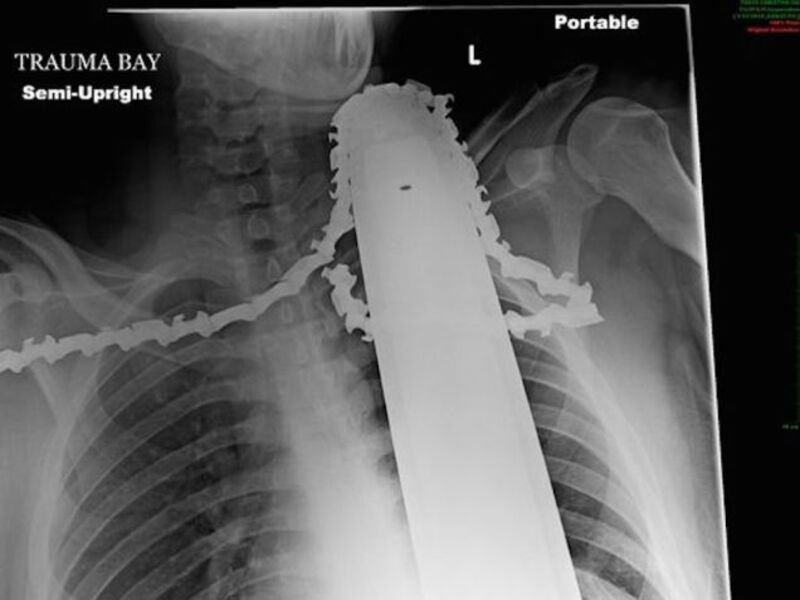

The latter happened to James Valentine on Monday afternoon in Ross Township, Pa. Valentine was working in a tree, sawing a branch while twenty feet off the ground, when he lost control of his chainsaw. The machine sawed a full two inches into his neck.

Mr. Valentine held the chainsaw in place with his right hand while hugging the trunk with his left arm to descend 5 feet in his rope harness with cleats on his shoes. Coworkers controlling the rope lowered him gently to sitting position on the ground. He leaned against one coworker, while another held the chainsaw steady. A third coworker worked to unbolt the blade from the heavy chainsaw motor without moving the blade.

Doctors at Allegheny General Hospital performed successful emergency surgery on Valentine, who somehow managed to avoid severing any major arteries or tendons.